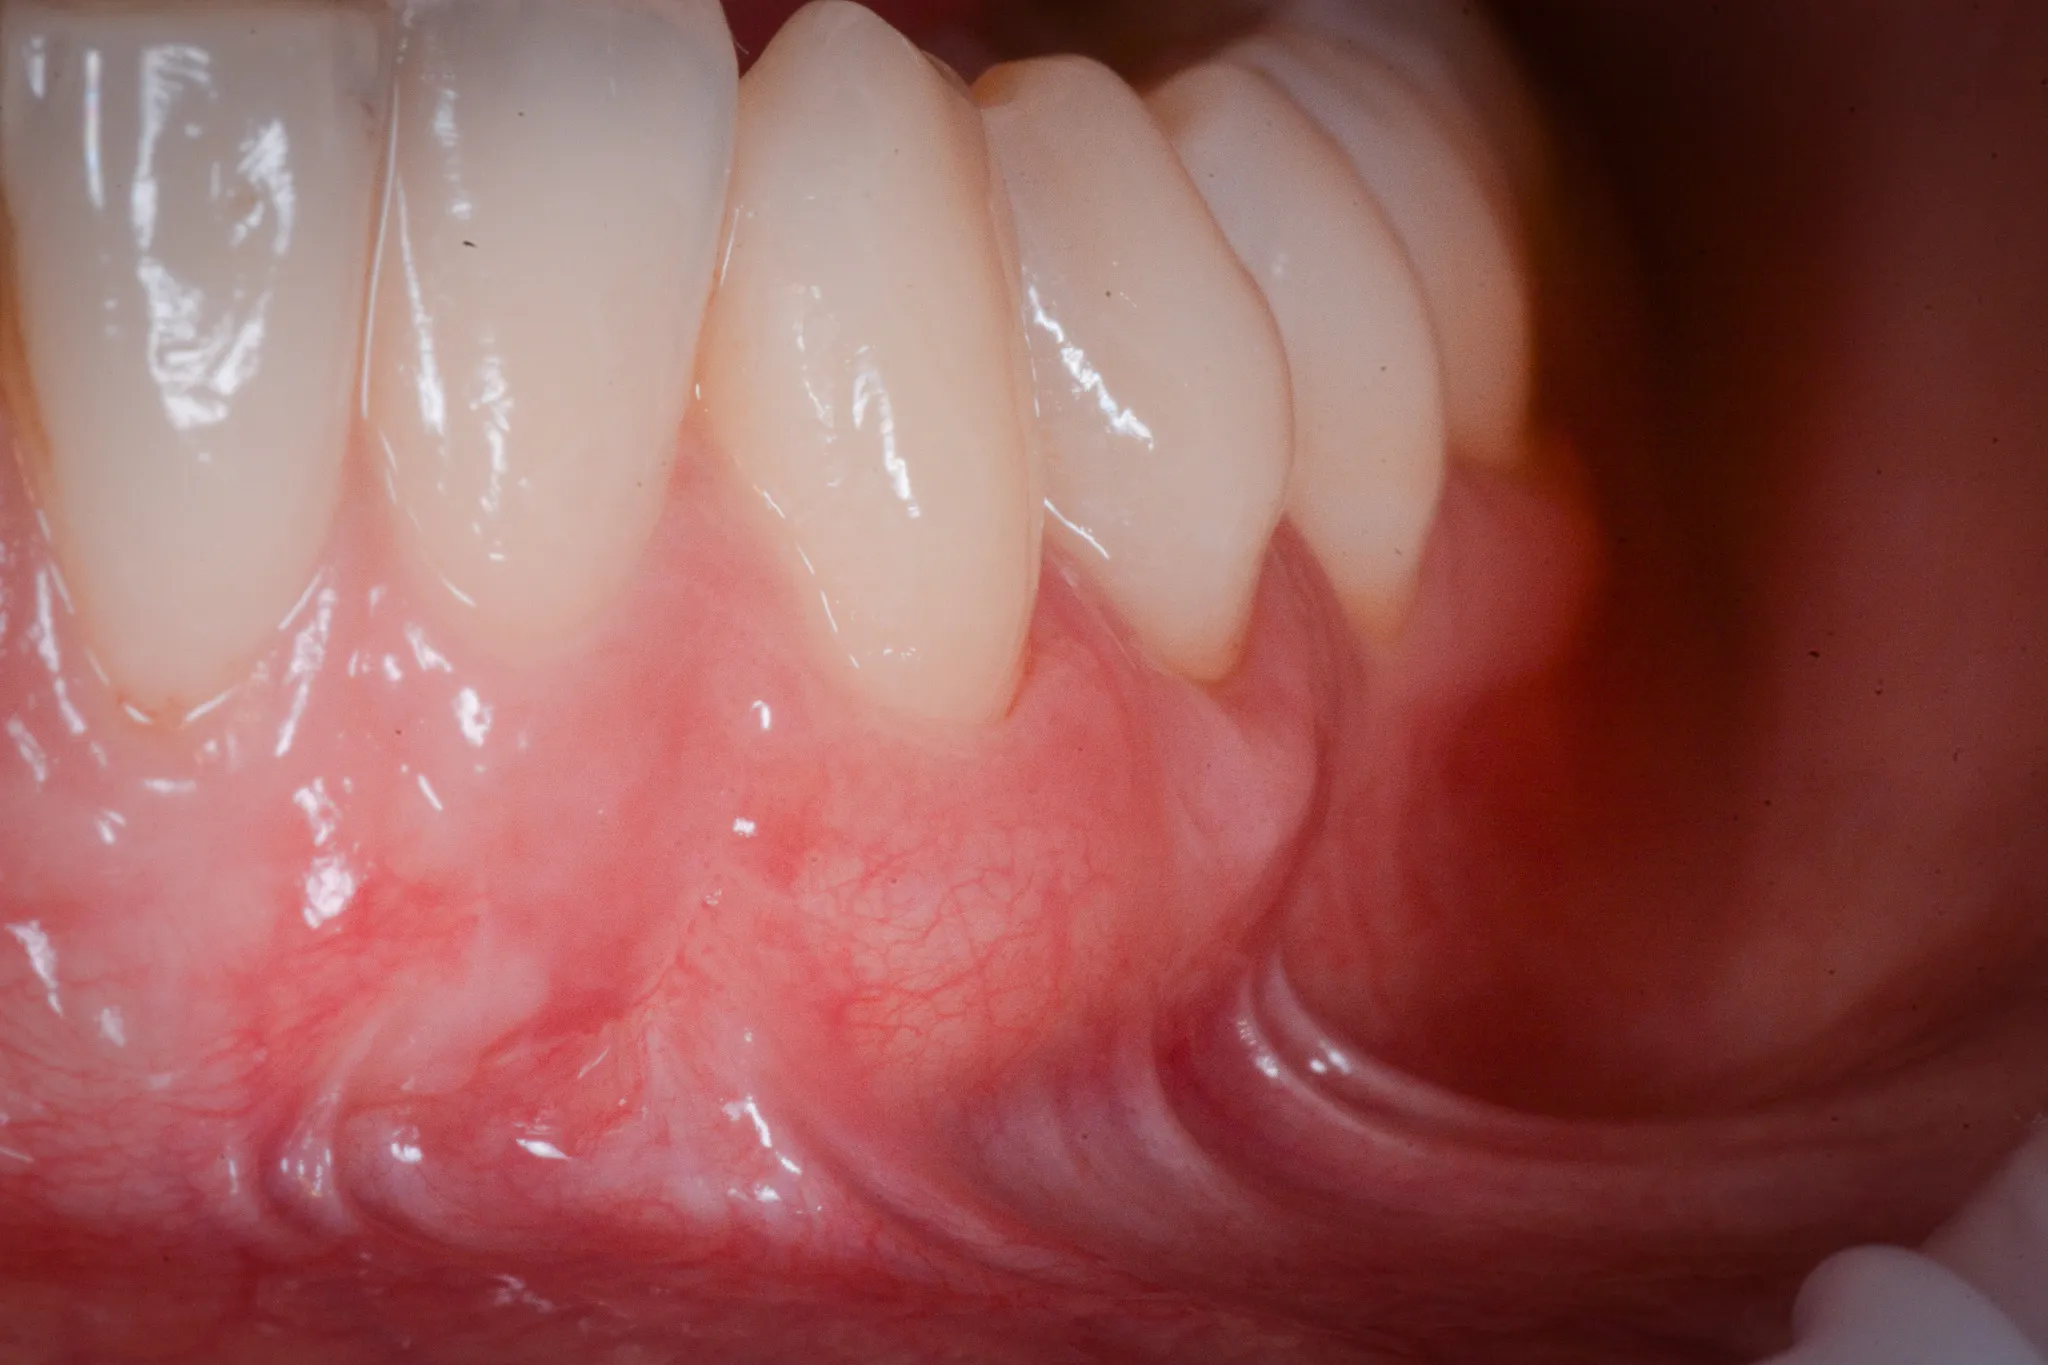

Il tessuto gengivale vero è un tessuto connettivo rivestito da epitelio cheratinizzato (in sostanza, un tessuto più spesso e resistente adeso all’osso sottostante). Quando si ritira, espone la radice del dente — una superficie che non è progettata per stare a contatto con l’ambiente orale. La radice è più porosa dello smalto, più vulnerabile alla carie, più sensibile agli stimoli termici.

Inoltre, a volte la gengiva si assottiglia per vari motivi lasciando spazio da un tessuto più delicato (mucosa orale) che è identico a quello che riveste le guancie e l’interno delle labbra.

Spazzolamento traumatico. Lo spazzolino rigido, usato con movimenti orizzontali e pressione eccessiva, abrade il margine gengivale sottile, soprattutto vestibolare. Il danno è cronico, progressivo, spesso unilaterale — il lato opposto alla mano dominante è quello più colpito.

Biotipo sottile. Alcune persone hanno gengive sottili per costituzione — una banda stretta di cheratinizzata, un periostio esile, una corticale ossea vestibolare ridotta a un velo. In questi pazienti, anche stimoli minimi possono innescare la recessione.

Malposizione dentale. Un dente vestibolarizzato, fuori dall’arco, ha meno osso e meno gengiva dalla parte esterna. La recessione è quasi inevitabile.

RT2 — Recessione con perdita di attacco interprossimale, ma inferiore o uguale a quella vestibolare. La prognosi è buona ma la copertura completa non è garantita.

RT3 — Recessione con perdita di attacco interprossimale superiore a quella vestibolare. Il supporto osseo tra i denti è compromesso. La copertura completa è improbabile.

In parole più semplici: se il livello dei tessuti interdentali è ancora conservato, il chirurgo può riportare la gengiva dove era. Se l’osso tra i denti non c’è più, il risultato sarà parziale ma migliorativo.